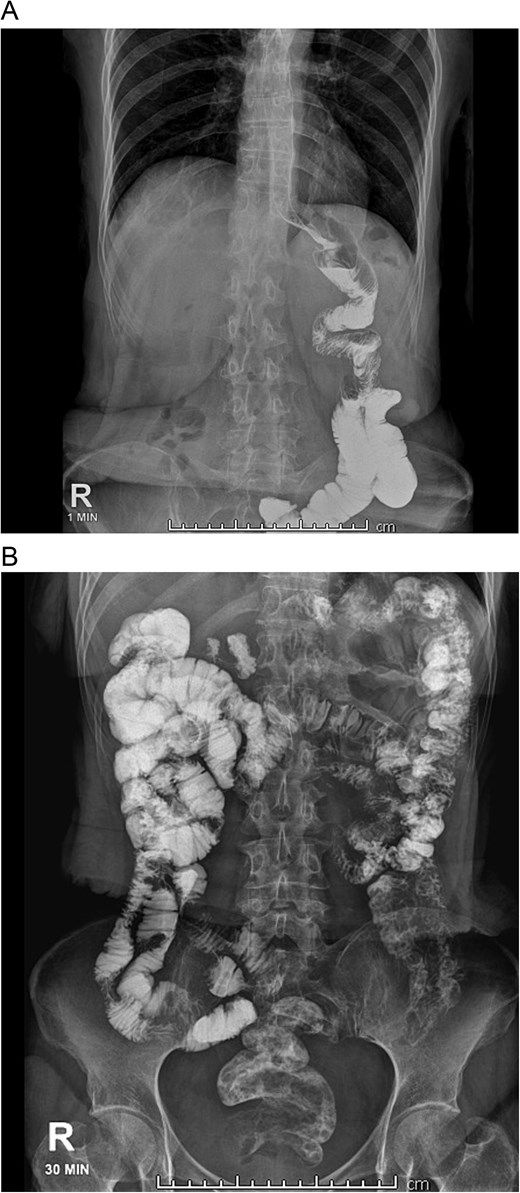

With these findings, a bypass reversal was decided. The alimentary limb was resected from the jejunal-jejunal anastomosis using mechanical staplers (Endo GIA 60 mm purple, COVIDIEN, North Haven, CT, USA), and a latero-lateral gastrostomy was performed between the gastric pouch and the gastric remnant without complications. A drain was placed after a negative methylene blue test, and surgery was completed without complications. Clear liquids were initiated on the first postoperative day without difficulties, and a new bowel transit time was done, which revealed no leaks and that the contrast reached the colon in 10 hours (Fig. 2A and 2B).

A: Bowel transit time, the whole stomach is seen connected. B: Bowel transit time, the whole stomach is seen along with the bowel.